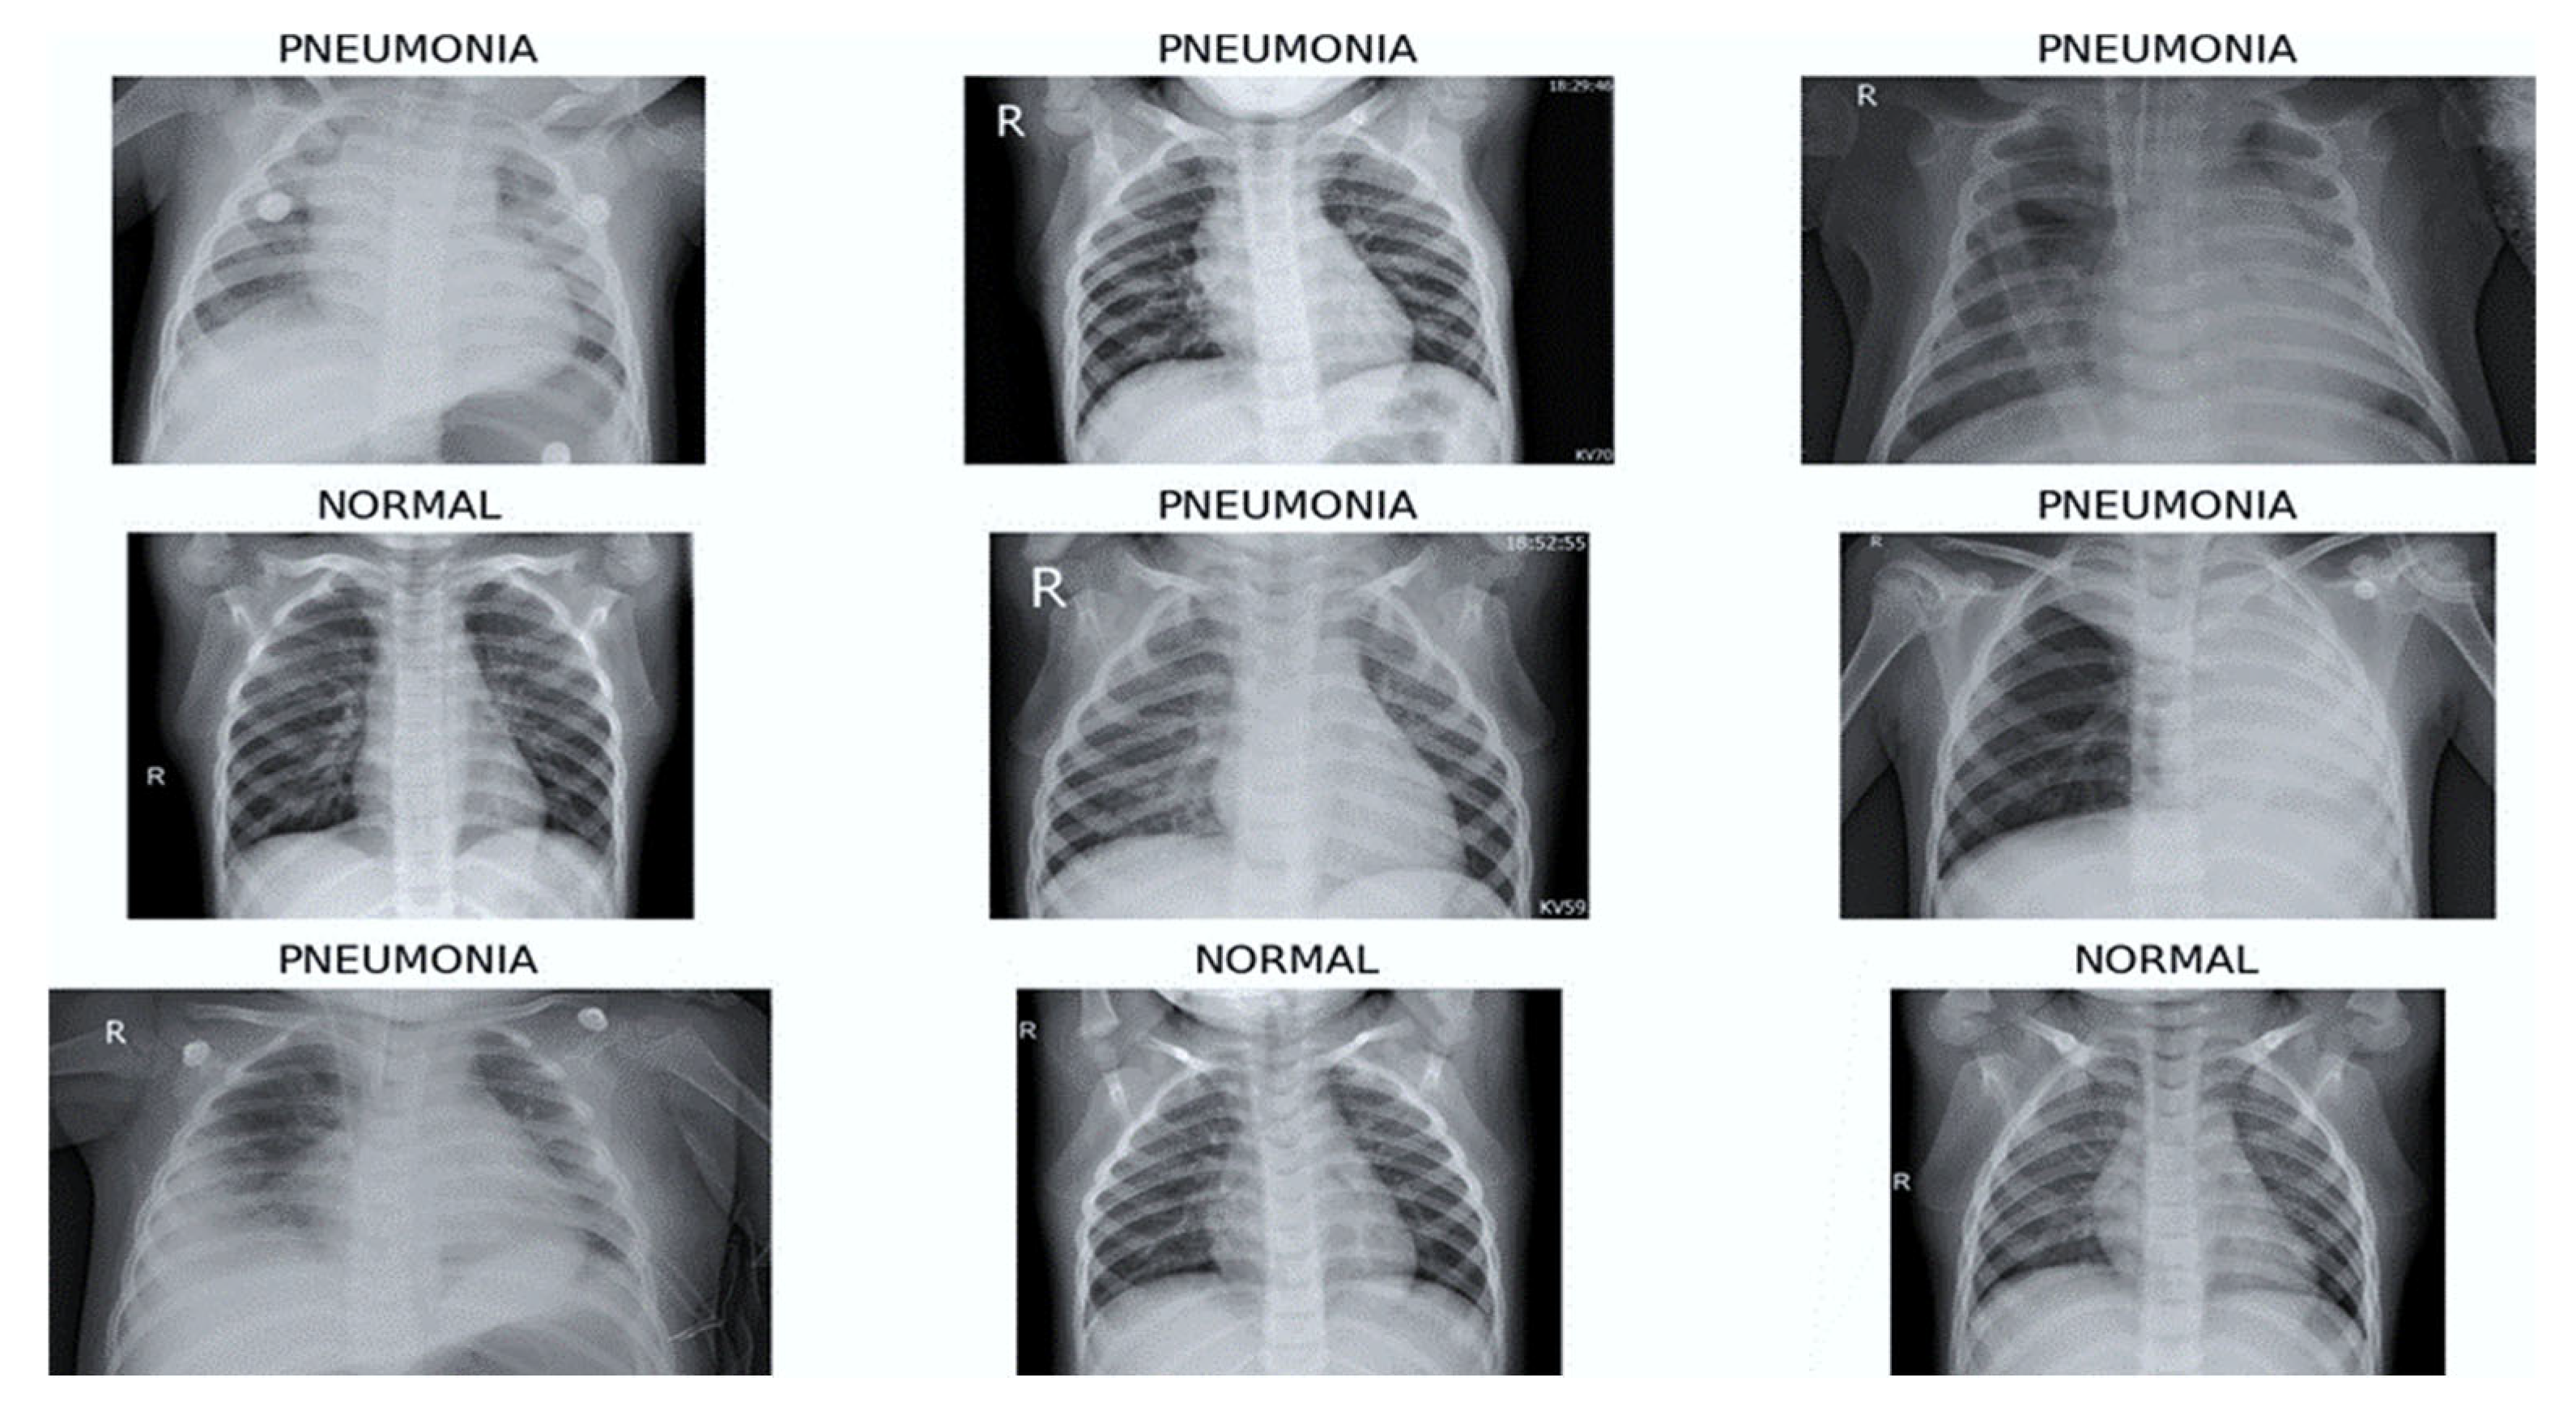

The dataset we chose to work with contains a large set of CXR images and was downloaded from Kaggle [30]. This dataset contains binary labels (‘Normal’ and ‘Pneumonia’) and does not differentiate between pneumonia subtypes such as bacterial, viral, fungal or atypical pneumonia. While this binary classification task is suitable for feasibility evaluation of an FL framework, it does not fully reflect the complexity of real-world clinical diagnosis. The CXR images from this dataset are anterior–posterior, meaning that the X-ray beam enters the body from the front (anterior) and exits through the back (posterior). The images are in JPEG format and have different dimensions (for example, 1782 × 1434, 1570 × 1164, etc.), but most of them have a high resolution (over 1000 pixels both in width and height). Their sizes range from 100 KB to 500 KB approximately, and they are labeled into two classes: normal and pneumonia. Some randomly selected images from the dataset are shown in Figure 2.